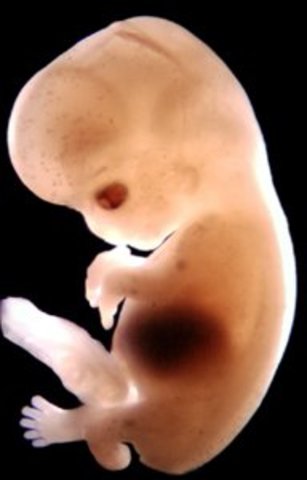

Week Seven Developments

The embryo's hands and feet are like paddles, but the fingers are slowly starting to shape. The fetus is also beginning to grow muscle fibers and now has it's own blood type.